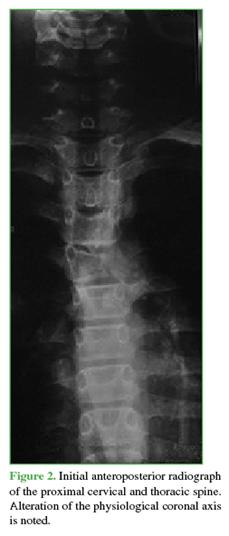

An initial anteroposterior radiograph showed an alteration in the physiological coronal axis (Figure 2).